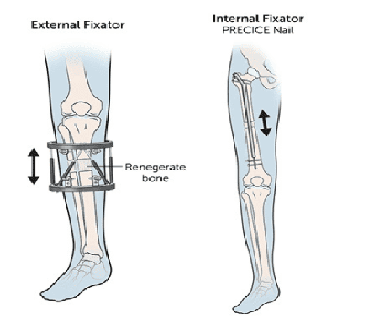

The bone is surgically cut, and a specialised lengthening device is attached to begin the gradual extension process.

The device is adjusted regularly to slowly separate the bone segments while your progress is closely monitored by doctors.

The limb lengthening procedures use the latest technology, including magnetically controlled internal nails and external fixators, allowing precise and gradual bone extension. These advanced methods support optimal bone regeneration while minimising discomfort and complications.